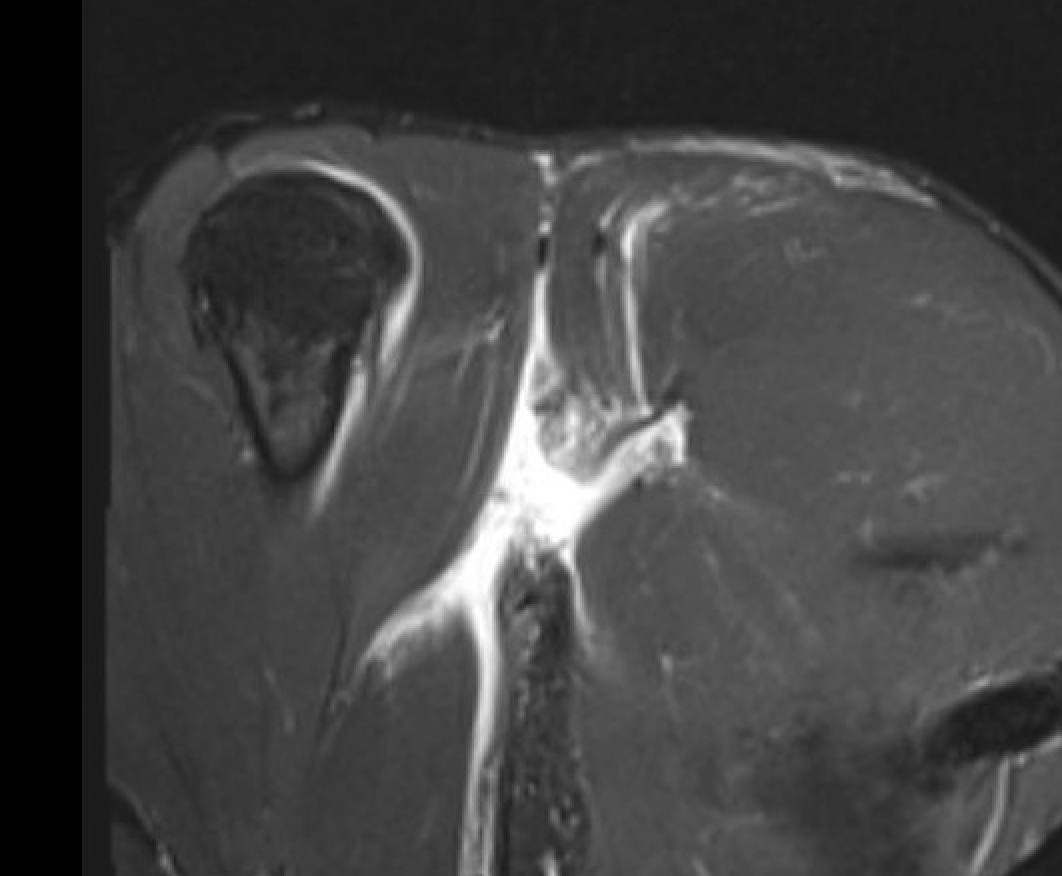

Axial T2 Right shoulder demonstrating tendon avulsion of both sternal and clavicular heads